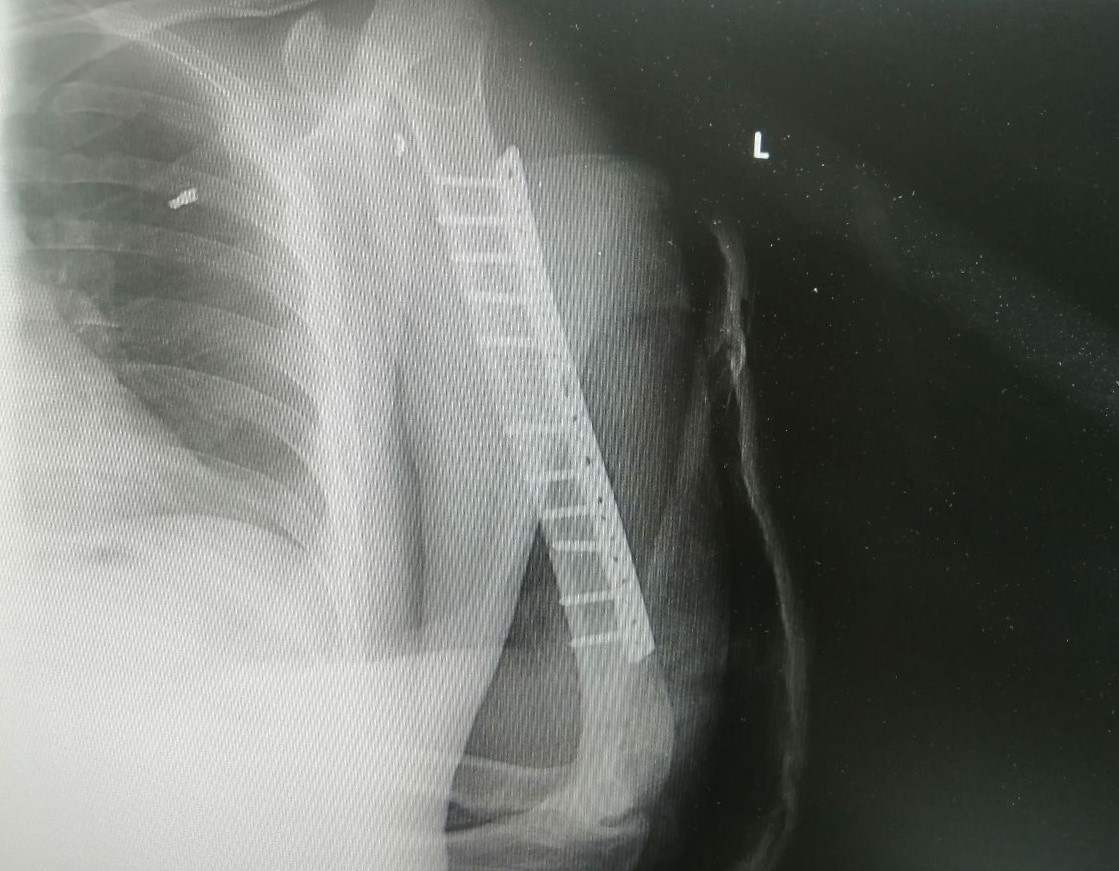

Травматологи-ортопеды Владимир Кельметр и Алексей Котов оперировали пациента более четырех часов. Целостность лучевого нерва они восстановили за счет фрагмента сурального нерва, который выделили из голени. Следующим этапом был остеосинтез плечевой кости. Её отломки соединили накостной пластиной, создав условия для скорейшей консолидации перелома.